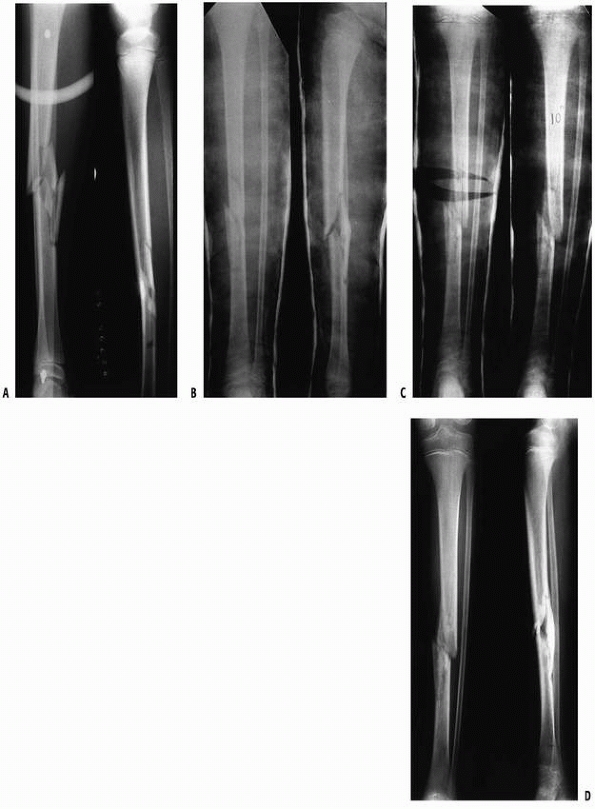

FIGURE 25-4 A.

Anteroposterior and lateral radiographs of the proximal tibial metaphyseal fracture with an intact fibula in a 3-year-old child. B. Anteroposterior and lateral radiograph in the initial long-leg cast demonstrate an acceptable alignment. C. Posttraumatic tibia valga is present 1 year after fracture union. (From Sharps CH, Cardea JA. Fractures of the shaft of the tibia and fibula. In: MacEwen GD, Kasser JR, Heinrich SD, eds. Pediatric Fractures: A Practical Approach to Assessment and Treatment. Baltimore: Williams & Wilkins, 1993:321, with permission.) |